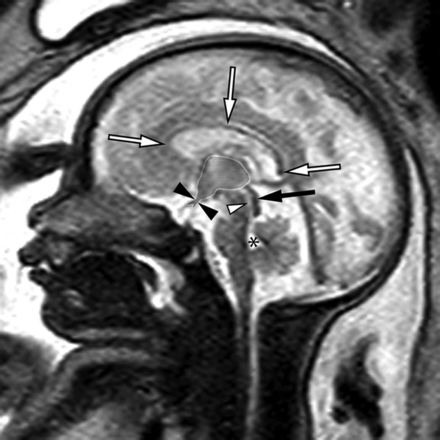

Sagittal single-shot fast spin-echo sequence of a 32-week fetus demonstrating normal midline anatomy. Note the fully formed corpus callosum (white arrows), normal tectum (black arrow), a patent cerebral aqueduct with normal intraluminal proportions (white arrowhead), and a normal fourth ventricle (asterisk). Note also the normal expected midline morphology of the third ventricle (light gray shaded area) with normal supraoptic and infundibular third ventricular recesses (black arrowheads).

Sagittal balanced steady-state free precession sequence from fetal MR imaging (A) of a 33-week fetus and a postnatal sagittal T1-weighted sequence (B) of the same patient demonstrating stenosis of the inferior cerebral aqueduct with associated aqueductal funneling (arrow). As a result, there is marked enlarged of the lateral and third ventricles with dilation of the inferior third ventricular recesses (white arrowheads) depicted by bowing of the lamina terminalis and inferior third ventricular floor. The corpus callosum is thin and superiorly bowed (black arrowheads). Note also the normal size of the fourth ventricle.